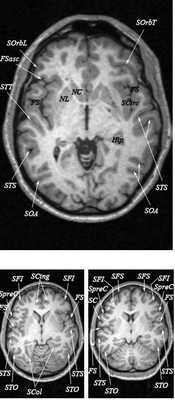

Анатомия головного мозга в МРТ изображении

МРТ головного мозга. Т2-взвешенная аксиальная МРТ. Цветовая обработка изображения.

Знание анатомии мозга очень важно для правильной локализации патологических процессов. Ещё более важно оно для изучения самого мозга с помощью современных «функциональных» методов, таких как функциональная магнитно-резонансная томография (fMRI), и позитронно-эмиссионная томография. С анатомией мозга мы знакомимся ещё со студенческой скамьи и существует множество анатомических атласов, в том числе и поперечных сечений. Казалось бы, зачем ещё один? На самом деле, сравнение МРТ срезов с анатомическими приводит к множеству ошибок. Это связано как со специфическими особенностями получения МРТ изображений, так и с тем, что строение мозга очень индивидуально.

Представленная страница сайта основана на специальном изучении МРТ головного мозга здоровых лиц. Для этого изображения получали с минимальной величиной воксела (1 мм в каждом измерении), что исключало наслоения борозд. Каждая из структур прослеживалась в трёх реконструированных плоскостях путём её выделения с помощью компьютерной программы. Мы рассматривали различные анатомические варианты, что обсуждается в работе. В результате, учитывая вариабельность строения мозга, подобран условно «стандартный» мозг. Поскольку на сайте нереально представить 128 срезов в каждой из основных плоскостей, мы ограничились только каждым пятым срезом. Основные срезы в поперечной плоскости даны без наклона назад (угол 0º). Под ними для представления о изменении соотношения анатомических структур демонстрируются срезы, выполненные на тех же уровнях, но с наклонами назад -15º и -30º.

Список сокращений

Борозды

Междолевые и срединные

SC - центральная борозда

FS - Сильвиева щель (латеральная борозда)

FSasc - восходящая ветвь Сильвиевой щели

FShor - поперечная борозда Сильвиевой щели

SPO - теменно-затылочная борозда

STO - височно-затылочная борозда

SCasc - восходящая ветвь поясной борозды

SsubP - подтеменная борозда

SCing - поясная борозда

SCirc - круговая борозда (островка)

SpreC - предцентральная борозда

SparaC - околоцентральная борозда

SFS - верхняя лобная борозда

FFM - лобно-краевая щель

SOrbL - латеральная глазничная борозда

SOrbT - поперечная глазничная борозда

SOrbM - медиальная глазничная борозда

SsOrb - подглазничная борозда

SCM - мозолисто-краевая борозда

SpostC - постцентральная борозда

SIP - внутритеменная борозда

STS - верхняя височная борозда

STT - поперечная височная борозда

SCirc - круговая борозда

SCalc - шпорная борозда

SOL - латеральная затылочная борозда

SOT - поперечная затылочная борозда

SOA - передняя затылочная борозда

Поперечные (аксиальные) МРТ срезы головного мозга